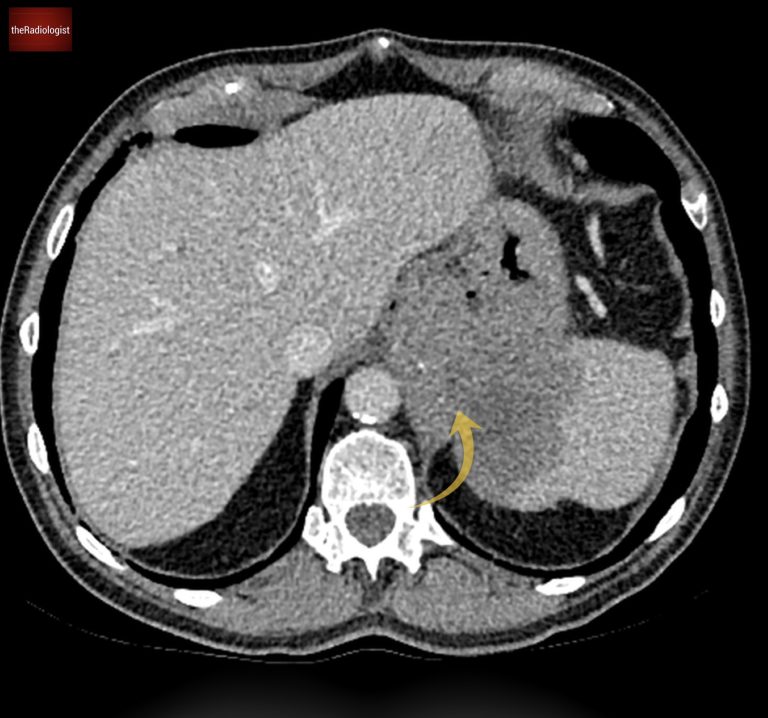

Let’s start with the stomach. The scan reveals an abnormality in the proximal stomach, specifically the gastric fundus. Here, there’s noticeable thickening of the stomach wall, and what’s more concerning is that it extends beyond the wall into the spleen.

Within the proximal stomach is a lesion that invades the spleen.

Moving on to the small bowel, take a closer look at the jejunal loops on the left side of the abdomen. There’s a segment of bowel that looks slightly dilated and shows long-segment thickening of the wall.

Interestingly, the bowel lumen isn’t narrowed, and there’s no significant upstream dilatation, so obstruction doesn’t appear to be an issue here.

Mural thickening of jejunal loops without narrowing of the bowel lumen.